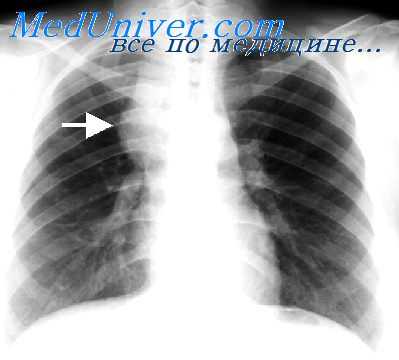

Всем больным необходимо производить прямую и боковую рентгенографию органов груди. У ряда больных очень показательные данные удается получить путем томографии. Для более рельефного выявления различных новообразований средостения большую ценность имеет так называемая пневмомедиастинография, т.е, рентгенография после введения в клетчатку средостения воздуха или кислорода, который вводят под местной анестезией за рукоятку грудины, под мечевидным отростком или около края грудины в одном из межреберных промежутков в количестве от 500 до 1000 см 3 . При анализе пневмомедиастинограмм – или пневмомедиастинотомо-грамм, который должен быть произведен квалифицированным рентгенологом, в большинстве случаев удается достаточно точно определить локализацию, размеры и другие особенности имеющегося новообразования.

При рентгенологическом исследовании больных с неврогенными опухолями обнаруживают округлую гомогенную тень, которая имеет ровные контуры и располагается в задних отделах средостения, примыкая к позвоночнику или к задним отрезкам ребер. Она особенно хорошо контурируется после наложения пневмомедиастинума или пневмоторакса.